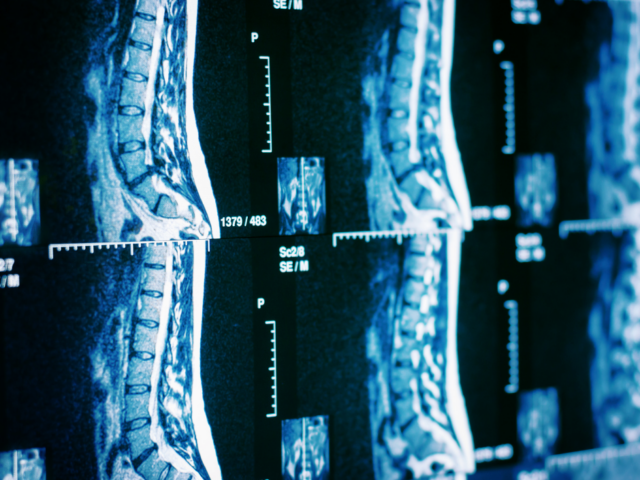

Orthopedic spine surgeon Alex Cruz, MD recently shared his expertise on the latest advancements in minimally invasive spine surgery and the lasting effects of the pandemic on orthopedics on Becker’s Healthcare Spine and Orthopedic Podcast.